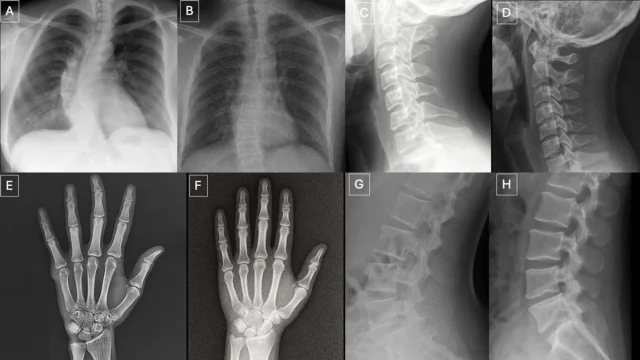

Um novo estudo publicado em 24 de março RadiologiaO Journal of the Radiological Society of North America (RSNA) mostra que tanto os radiologistas quanto os modelos multimodais de grande linguagem (LLM) têm dificuldade em distinguir entre raios X reais e imagens “profundamente falsas” geradas pela inteligência artificial (IA). As descobertas levantam preocupações sobre os riscos representados pelas imagens médicas sintéticas e destacam a necessidade de melhores ferramentas e formação para ajudar a proteger a precisão das imagens médicas e preparar os profissionais de saúde para identificar deepfakes.

O estudo incluiu 17 radiologistas de 12 instituições de 6 países (Estados Unidos, França, Alemanha, Turquia, Reino Unido e Emirados Árabes Unidos). Sua experiência varia de iniciantes a especialistas com até 40 anos de experiência prática. O estudo examinou um total de 264 imagens de raios X, divididas igualmente entre varreduras reais e imagens geradas por IA.

Os participantes visualizaram dois conjuntos independentes de imagens sem sobreposição. Um conjunto contém uma mistura de imagens reais e raios X gerados pelo ChatGPT de diferentes partes do corpo. O segundo grupo se concentrou em radiografias de tórax, metade reais e metade criadas usando RoentGen, um modelo de difusão de inteligência artificial generativa de código aberto desenvolvido por pesquisadores da Faculdade de Medicina da Universidade de Stanford.

Quando os radiologistas não foram informados de que continham imagens falsas, apenas 41% dos radiologistas aprovaram os raios X gerados por IA após avaliarem a sua qualidade técnica. Depois que souberam da presença de imagens sintéticas, a precisão média na distinção entre imagens reais e falsas aumentou para 75%.

O desempenho varia amplamente entre os indivíduos. Os radiologistas identificaram corretamente de 58% a 92% das imagens produzidas pelo ChatGPT. Os sistemas de inteligência artificial apresentam limitações semelhantes. Quatro LLMs multimodais – GPT-4o (OpenAI), GPT-5 (OpenAI), Gemini 2.5 Pro (Google) e Llama 4 Maverick (Meta) – alcançaram taxas de precisão que variam de 57% a 85%. Mesmo o ChatGPT-4o, usado para gerar imagens deepfake, não detectou todas as imagens, embora tenha tido um desempenho melhor que outros modelos.

Para radiografias de tórax geradas pelo RoentGen, a precisão dos radiologistas variou de 62% a 78%, enquanto a precisão do modelo de IA variou de 52% a 89%.

Dicas visuais em raios X deepfake

Os pesquisadores descobriram vários padrões que podem aparecer nas imagens compostas.

“Imagens médicas deepfake muitas vezes parecem perfeitas demais”, disse o Dr. Todjman. “Os ossos são muito lisos, a coluna vertebral é anormalmente reta, os pulmões são muito simétricos, o padrão dos vasos sanguíneos é muito uniforme e as fraturas parecem incomumente limpas e consistentes, muitas vezes limitadas a um lado do osso”.